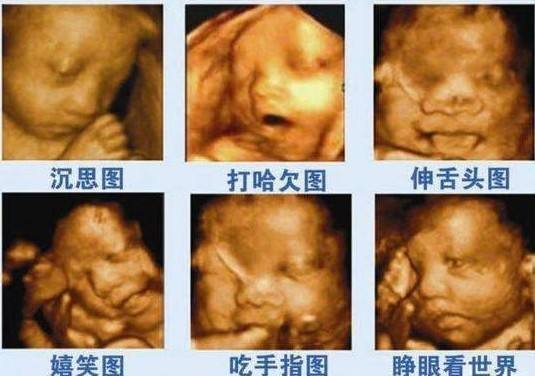

第二,四维前1、2周,多和胎宝宝沟通。

孕妈约好四维后,可以在四维前1、2周就开始和宝宝说话,请宝贝配合医生一些。

胎儿在第8周耳廓已经形成;在孕25周,胎儿的传音系统基本发育完成;孕28周时,胎儿的传音系统已经充分发育完成,并会发生听觉反应了。

因此准爸爸、准妈妈平时也可以多和胎宝宝说说话、唱唱歌、讲讲故事。

甜的食物,不管是四维时,还是后期的胎心监护,都能让胎儿更活泼些,方便医生观察胎儿。

四维前半小时,可以食用一些葡萄、樱桃等水果,或蛋糕、奶糖、功能性饮料(宝矿力、脉动、尖叫,不推荐红牛,不适合孕妇)。

不要吃巧克力,不适宜胎儿。

等到做四维的时候,刚好胎儿也能有反应了。